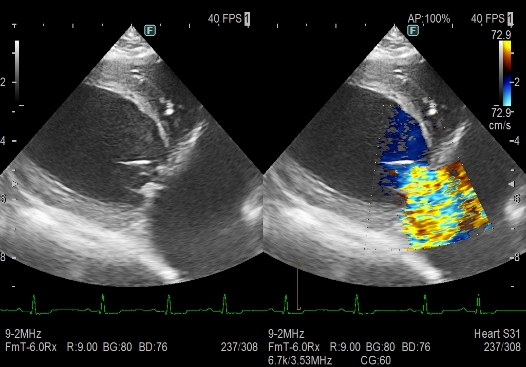

心臓超音波検査(心臓の大きさや弁、血管の異常の有無の評価)